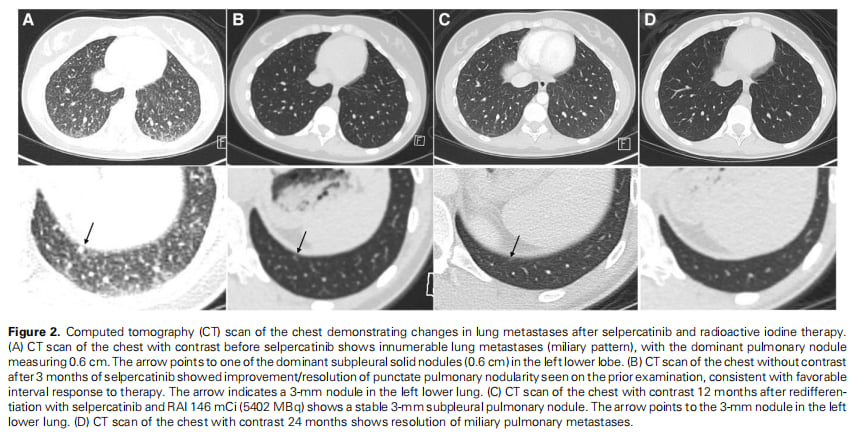

- 影像学完全缓解:更令人振奋的是,胸部CT扫描显示,在治疗后18个月,患者的肺部结节已完全消失,并在24个月时得以维持。患者实现了影像学上的完全缓解。

▲图2 胸部CT扫描显示塞普替尼联合放射性碘治疗后肺转移灶的变化